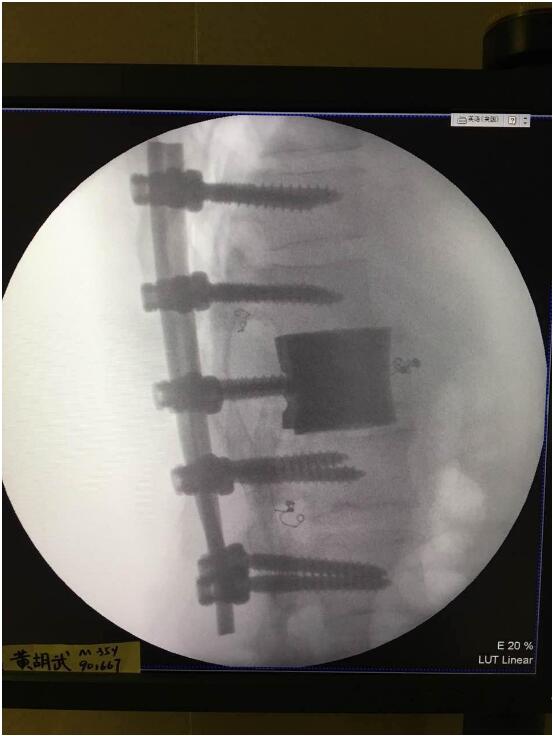

2018年2月7日華鈦三維與南方醫(yī)院脊柱骨外科聯(lián)合澳大利亞技術(shù)科學(xué)與工程院吳鑫華院士領(lǐng)導(dǎo)的莫納什大學(xué)增材制造研究中心合作的世界第一例3D打印個(gè)性化“人工椎體/椎間盤一體化“植入手術(shù)成功實(shí)施。不僅保住了病人的脊椎,還保住了其日后的活動(dòng)能力。

這次手術(shù)是廣州華鈦三維骨科研究中心(華鈦三維骨科研究院)與南方醫(yī)院聯(lián)合澳大利亞技術(shù)科學(xué)與工程院吳鑫華院士領(lǐng)導(dǎo)的莫納什大學(xué)增材制造研究中心合作的世界第一例3D打印個(gè)性化人工椎體/腰間盤一體化植入手術(shù)。南方醫(yī)院脊椎及骨病外科鄭明輝副主任醫(yī)師在嶺南名醫(yī)陳建庭主任和朱青安教授指導(dǎo)下,與華鈦三維工程師陸國(guó)贊合作構(gòu)思設(shè)計(jì),澳大利亞莫納什大學(xué)增材制造研究中心主任吳鑫華院士團(tuán)隊(duì)進(jìn)行了一個(gè)多月的個(gè)性化鈦合金3D打印工藝研究,成功打印出符合病人要求的人工椎體/腰間盤一體化植入物。這次手術(shù)的成功,標(biāo)志著中國(guó)的3D打印植入物技術(shù)在骨科醫(yī)療領(lǐng)域達(dá)到世界先進(jìn)水平。

為了更好的完成手術(shù),陳建庭主任、鄭明輝副主任醫(yī)師等骨科專家與華鈦三維的3D打印專家從2017年10月份開始籌備該手術(shù)??紤]到每一個(gè)病人的脊椎形狀都存在差異,骨科專家認(rèn)為用一個(gè)現(xiàn)成的標(biāo)準(zhǔn)植入物不大可能匹配病人的生理參數(shù)。醫(yī)學(xué)專家和3D打印專家根據(jù)病人脊柱的CT掃描數(shù)據(jù),為病人的脊柱建立了精準(zhǔn)的3D圖像。根據(jù)這個(gè)圖像,治療團(tuán)隊(duì)就能夠設(shè)計(jì)并定制出屬于病人的個(gè)性化植入物。為了使個(gè)性化定制的人工椎體與病人椎體之間更好的融合,手術(shù)實(shí)施前治療團(tuán)隊(duì)先后設(shè)計(jì)了100多個(gè)方案,制作了數(shù)十個(gè)植入物的術(shù)前模型進(jìn)行研討。事實(shí)證明,手術(shù)最終使用的植入物是最適合手術(shù)和病人身體情況的。

利用3D打印技術(shù)生產(chǎn)出來的人工椎體是完全按照患者的解剖結(jié)構(gòu)完成脊椎結(jié)構(gòu)重建及固定的, 裝上一枚精準(zhǔn)的、個(gè)性化的人工脊椎,患者康復(fù)后完全可以正常地生活和工作。過去這種手術(shù)常常是使用鈦網(wǎng)內(nèi)填入自體或異體碎骨作為椎體間支撐材料,但鈦網(wǎng)一旦移位壓迫脊髓,患者就會(huì)有癱瘓的風(fēng)險(xiǎn)。這次手術(shù)中的脊椎植入物內(nèi)部具有經(jīng)過力學(xué)優(yōu)化設(shè)計(jì)的晶格結(jié)構(gòu),比傳統(tǒng)鈦網(wǎng)具有更強(qiáng)的承重力,金屬3D打印可以直接制造出這樣的復(fù)雜結(jié)構(gòu)。

最終在經(jīng)歷近八個(gè)小時(shí)后,病人的家屬終于等到了好消息:人工椎體/椎間盤一體化金屬植入物成功植入,手術(shù)順利。由于病人術(shù)中出血量小,生命體征平穩(wěn),他不用進(jìn)入ICU觀察,直接回到了普通病房。“現(xiàn)在我們都很高興,成功做出了世界首例人工椎體/椎間盤一體化金屬植入物,病人今后可以與常人一樣工作和生活。”鄭明輝醫(yī)生說。